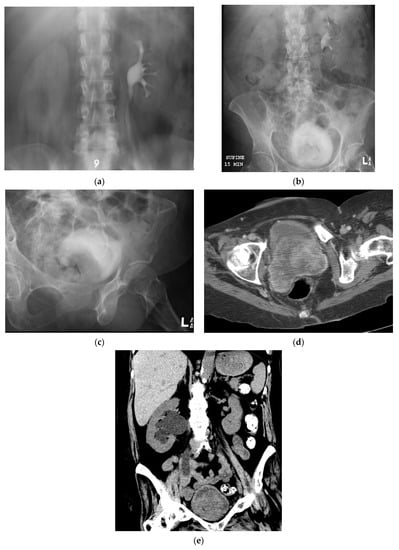

5.5. Fluoroscopic/Radiographic Techniques